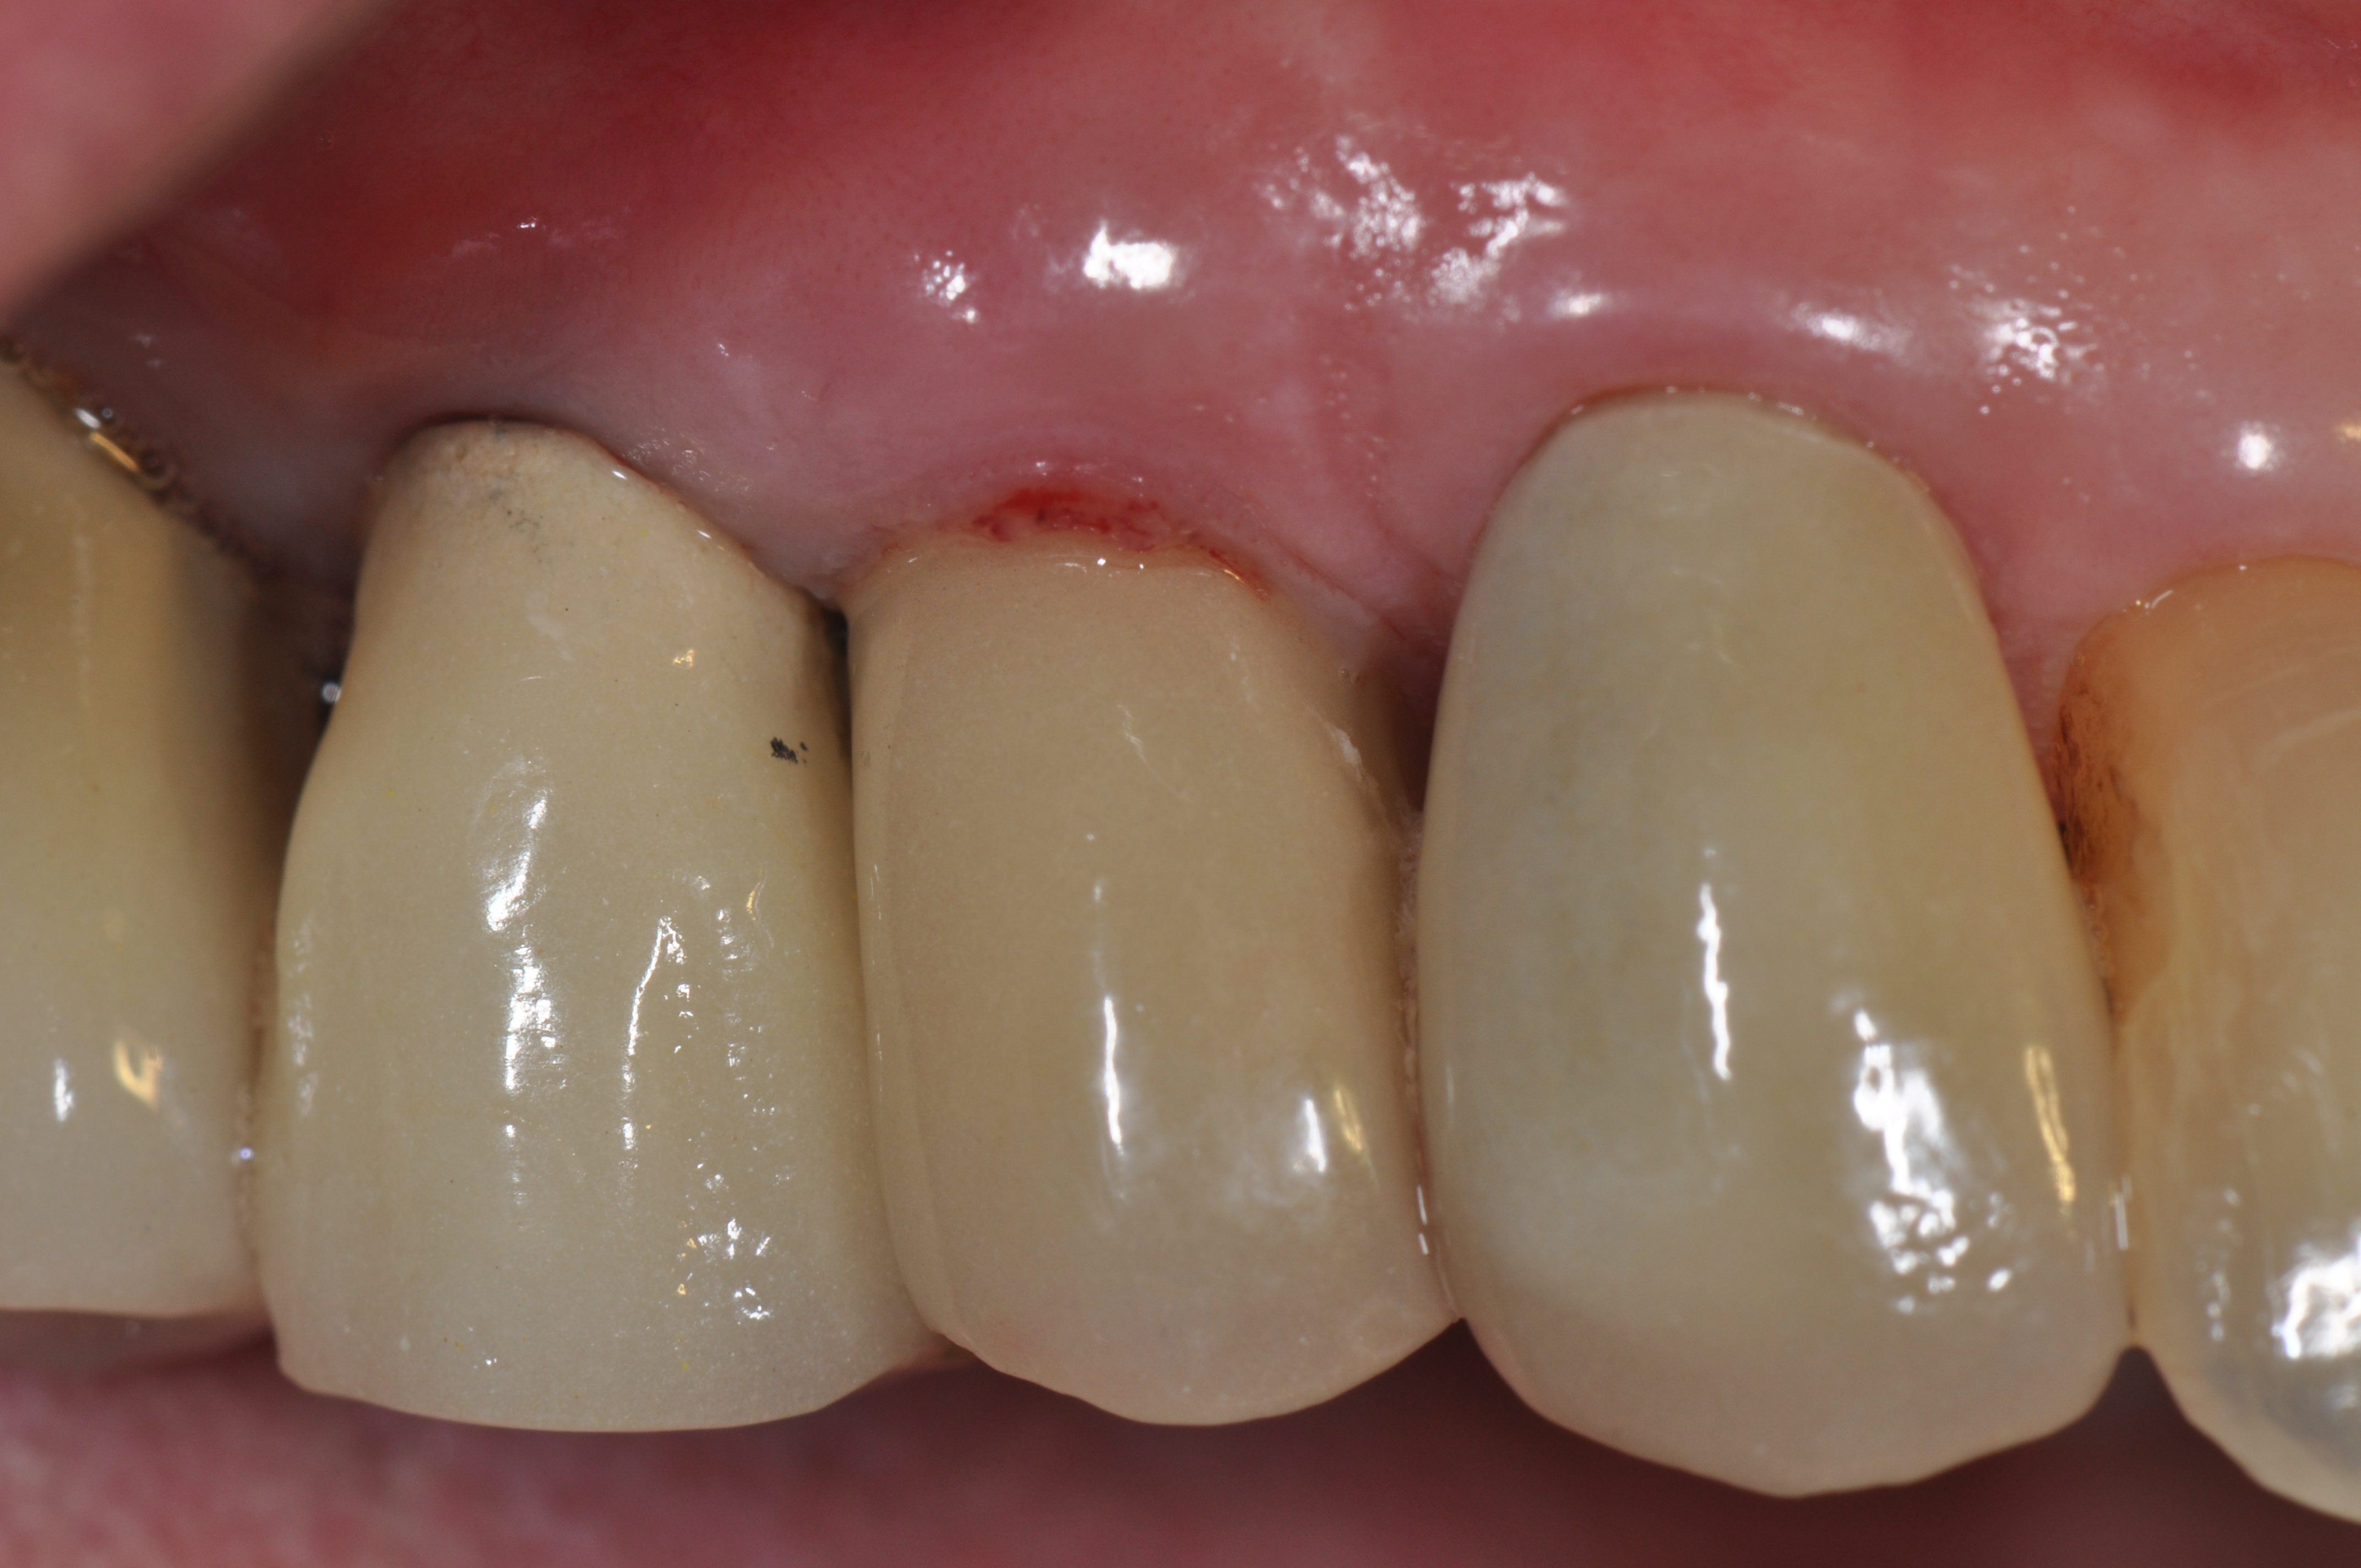

Fig 6. A clinical view of this area suggests that peri-implant mucositis is present. The tissue is swollen, it bleeds on probing, has 5 mm of probing depth, and exhibits purulent exudate.

Figure 6